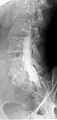

Conventional myelography in oblique projection. You can see the individual nerve root sheaths.

Computed tomography after conventional myelography. The overlap-free representation often allows a more secure assessment. The high density of contrast material may be troublesome in case of insufficient mixing prior to CT.